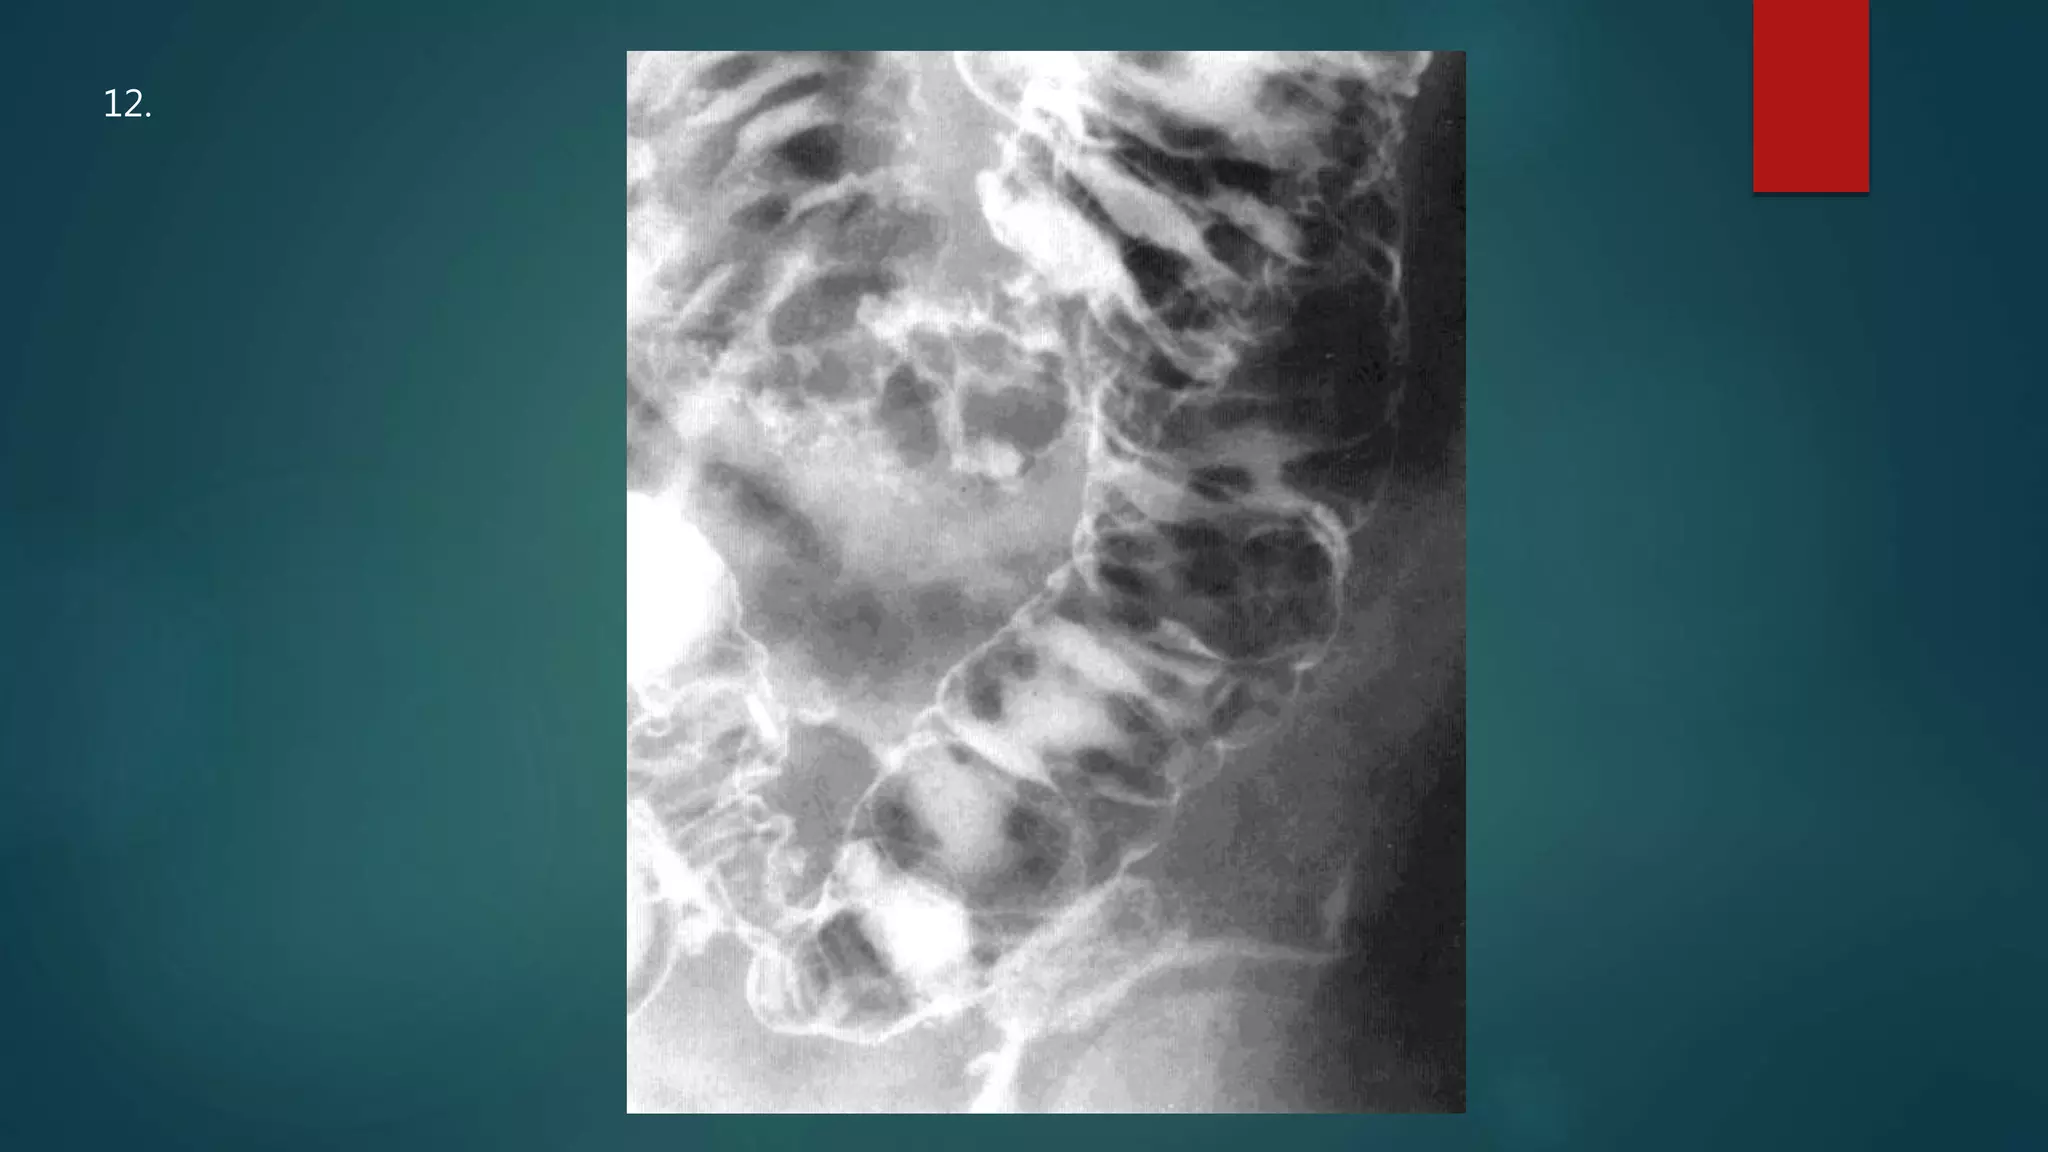

This document appears to be a medical report discussing several patients. It mentions a 35-year-old who was in a severe motor vehicle accident and an 81-year-old with a history of a non-vegetarian diet who had a perforated bowel from a chicken bone. The document provides few other details across its 25 numbered entries and was authored by Dr. Anish Choudhary for junior year 3 on May 30, 2016.